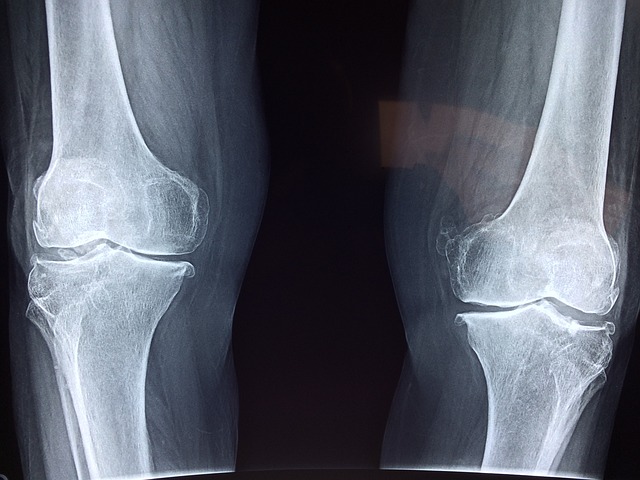

골관절염은 관절의 연골이 마모되어 발생하는 퇴행성 질환으로, 주로 무릎, 손, 엉덩이, 척추 관절에서 발생하며, 통증, 부종, 운동 범위 감소 등의 증상을 유발합니다. 콘드로이친은 이러한 골관절염의 증상을 완화하는 데 도움을 줄 수 있는 것으로 알려져 있습니다.

연구에 따르면, 콘드로이친을 정기적으로 섭취한 환자들은 통증 감소와 함께 관절의 유연성이 개선되었다고 보고합니다. 이는 콘드로이친이 연골 조직을 보호하고, 연골의 손상을 줄이며, 연골 내의 수분 및 영양소 보유 능력을 향상하기 때문으로 해석됩니다.

더욱이, 콘드로이친은 관절염의 진행을 늦추는 데에도 긍정적인 영향을 미칠 수 있음을 시사하는 연구 결과가 있습니다. 이는 장기적으로 관절의 건강을 유지하고, 추가적인 관절 손상을 방지하는 데 중요할 수 있습니다.